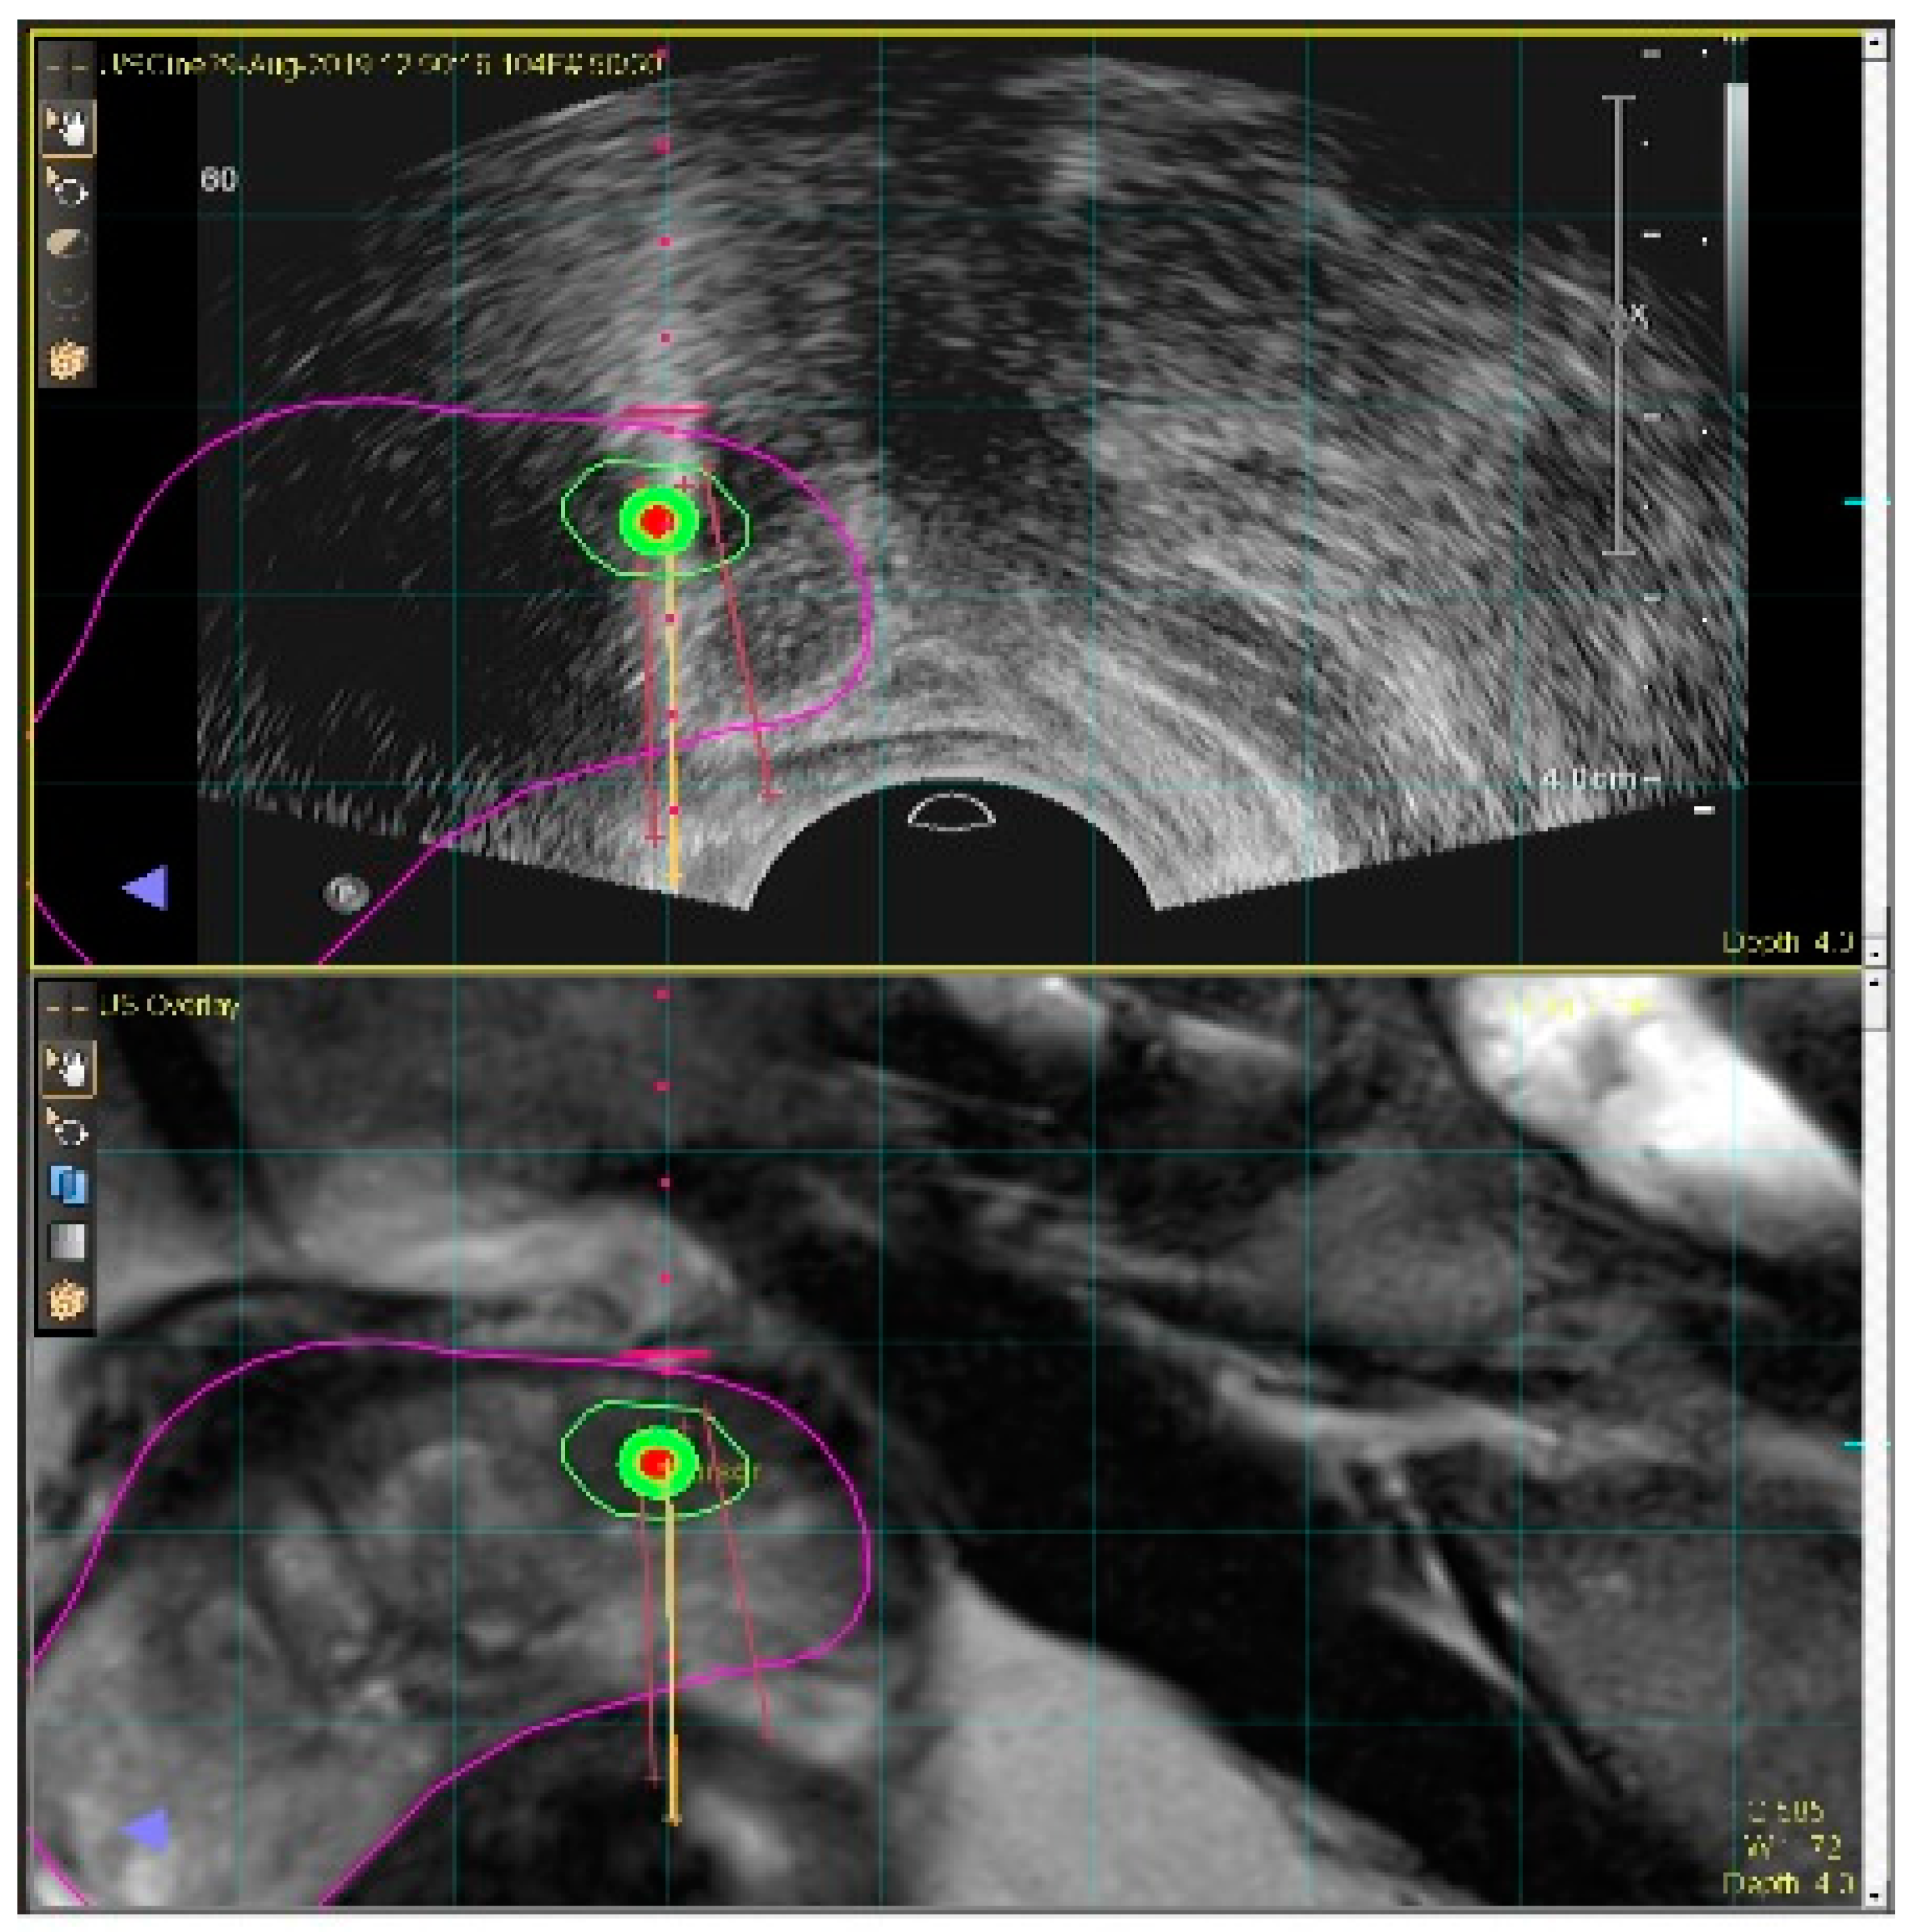

Generally, transrectal (TR), or transperineal (TP), ultrasound images serve as the main guidance for prostate biopsies. However, they display poor contrast between healthy and cancerous regions. On the other hand, MRI, or mpMRI, is currently the mainstay for the detection and localization of PCas, and MRI-guided targeted biopsy pathways have been shown to increase the detection of clinically significant prostate cancer [4]. However, in-bore MRI-based interventions are cumbersome and consume valuable magnet scan time. As a result, MRI–US fusion techniques are increasingly favoured (Figure 5).

Figure 5.

MRI–US fusion technique for targeted prostate biopsy requires precise registration between pre-operative prostate MRI (bottom image) and real-time ultrasound (top image).